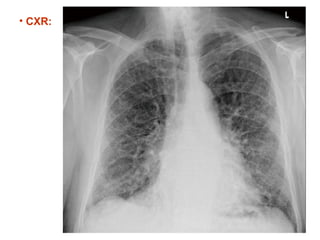

A 63-year-old male with a history of prostate adenocarcinoma and COPD presented with worsening dyspnea on exertion and significant weight loss. Examination revealed paraseptal emphysema and combined pulmonary fibrosis with emphysema syndrome (CPFE), with evidence of pulmonary hypertension. Despite partial improvement with steroids, the patient experienced progressive symptoms, necessitating further investigations.